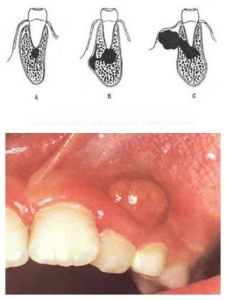

化膿性根尖周炎的排膿途徑:急性根尖周膿腫最常見的排膿途徑是經黏膜下(或皮下)排膿,即通過根尖區骨松質到達牙槽骨的骨外板,經外板的哈弗管到達骨膜下形成骨膜下膿腫。由於骨膜緻密,隨膿腫壓力最大,疼痛達到最高峰,常伴有全身不適,體溫升高,白細胞增多,區域淋巴結腫大、觸痛。一旦膿液穿破骨膜達黏膜下(或皮下)時疼痛緩解。

(2)慢性根尖周膿腫:多無自覺症狀,在患牙的根尖區黏膜處可有瘺管,瘺管口處常有肉芽組織增生,可有膿液自瘺管排出,因有瘺管引流,不易轉為急性炎症。

(3)根尖囊腫:多無自覺症狀,牙齒變色,牙片可顯示根尖部的囊腫,若囊腫增大,迫使周圍骨質吸收,在患牙根尖部黏膜多呈半圓形隆起,有桌球感。